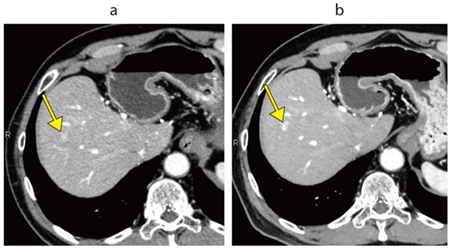

Aquilion ONE / INSIGHT Editionは、ハードウエア系の一新で0.24秒のガントリ回転速度など基本性能を向上させ、AI技術によって開発された超解像画像再構成技術「Precise IQ Engine(PIQE)」、モーションアーチファクト低減技術「CLEAR Motion」などを搭載したフラッグシップCTである。画像の評価を佐藤部長は、「PIQEによる再構成は予想以上にノイズが低減されており、従来と同等の線量でも大きく画質が向上しています。血管系の精度向上はもちろんですが、肝実質や膵実質など実質臓器についてもノイズの低減で読影がしやすくなっています。読影では消化管も見ていますが、解像度の向上とPIQEによってクリアに描出されて、管腔構造の連続性が認識しやすく、壁構造のコントラストが向上して粘膜変化をとらえやすくなっており評価が容易になっていると感じます」と述べる。PIQEは肺野を除く全例で適用されている。肝細胞がんの症例(図1)では、3か月前にIVR-CTの80列で撮影した画像に比べて、ほぼ同条件で撮ったAquilion ONE / INSIGHT Editionの画像では早期濃染を示す小病変がより明瞭に描出されている。また、胃潰瘍の症例では、通常の造影検査で粘膜の欠損や粘膜下の浮腫が明瞭に描出されていた。佐藤部長は、「従来は小さい消化管病変は疑いを指摘するにとどまっていましたが、より確信を持って診断できます」と述べる。

図1 肝細胞がん

a:Aquilion PRIME(AIDR 3D*)

b:Aquilion ONE / INSIGHT Edition(PIQE)